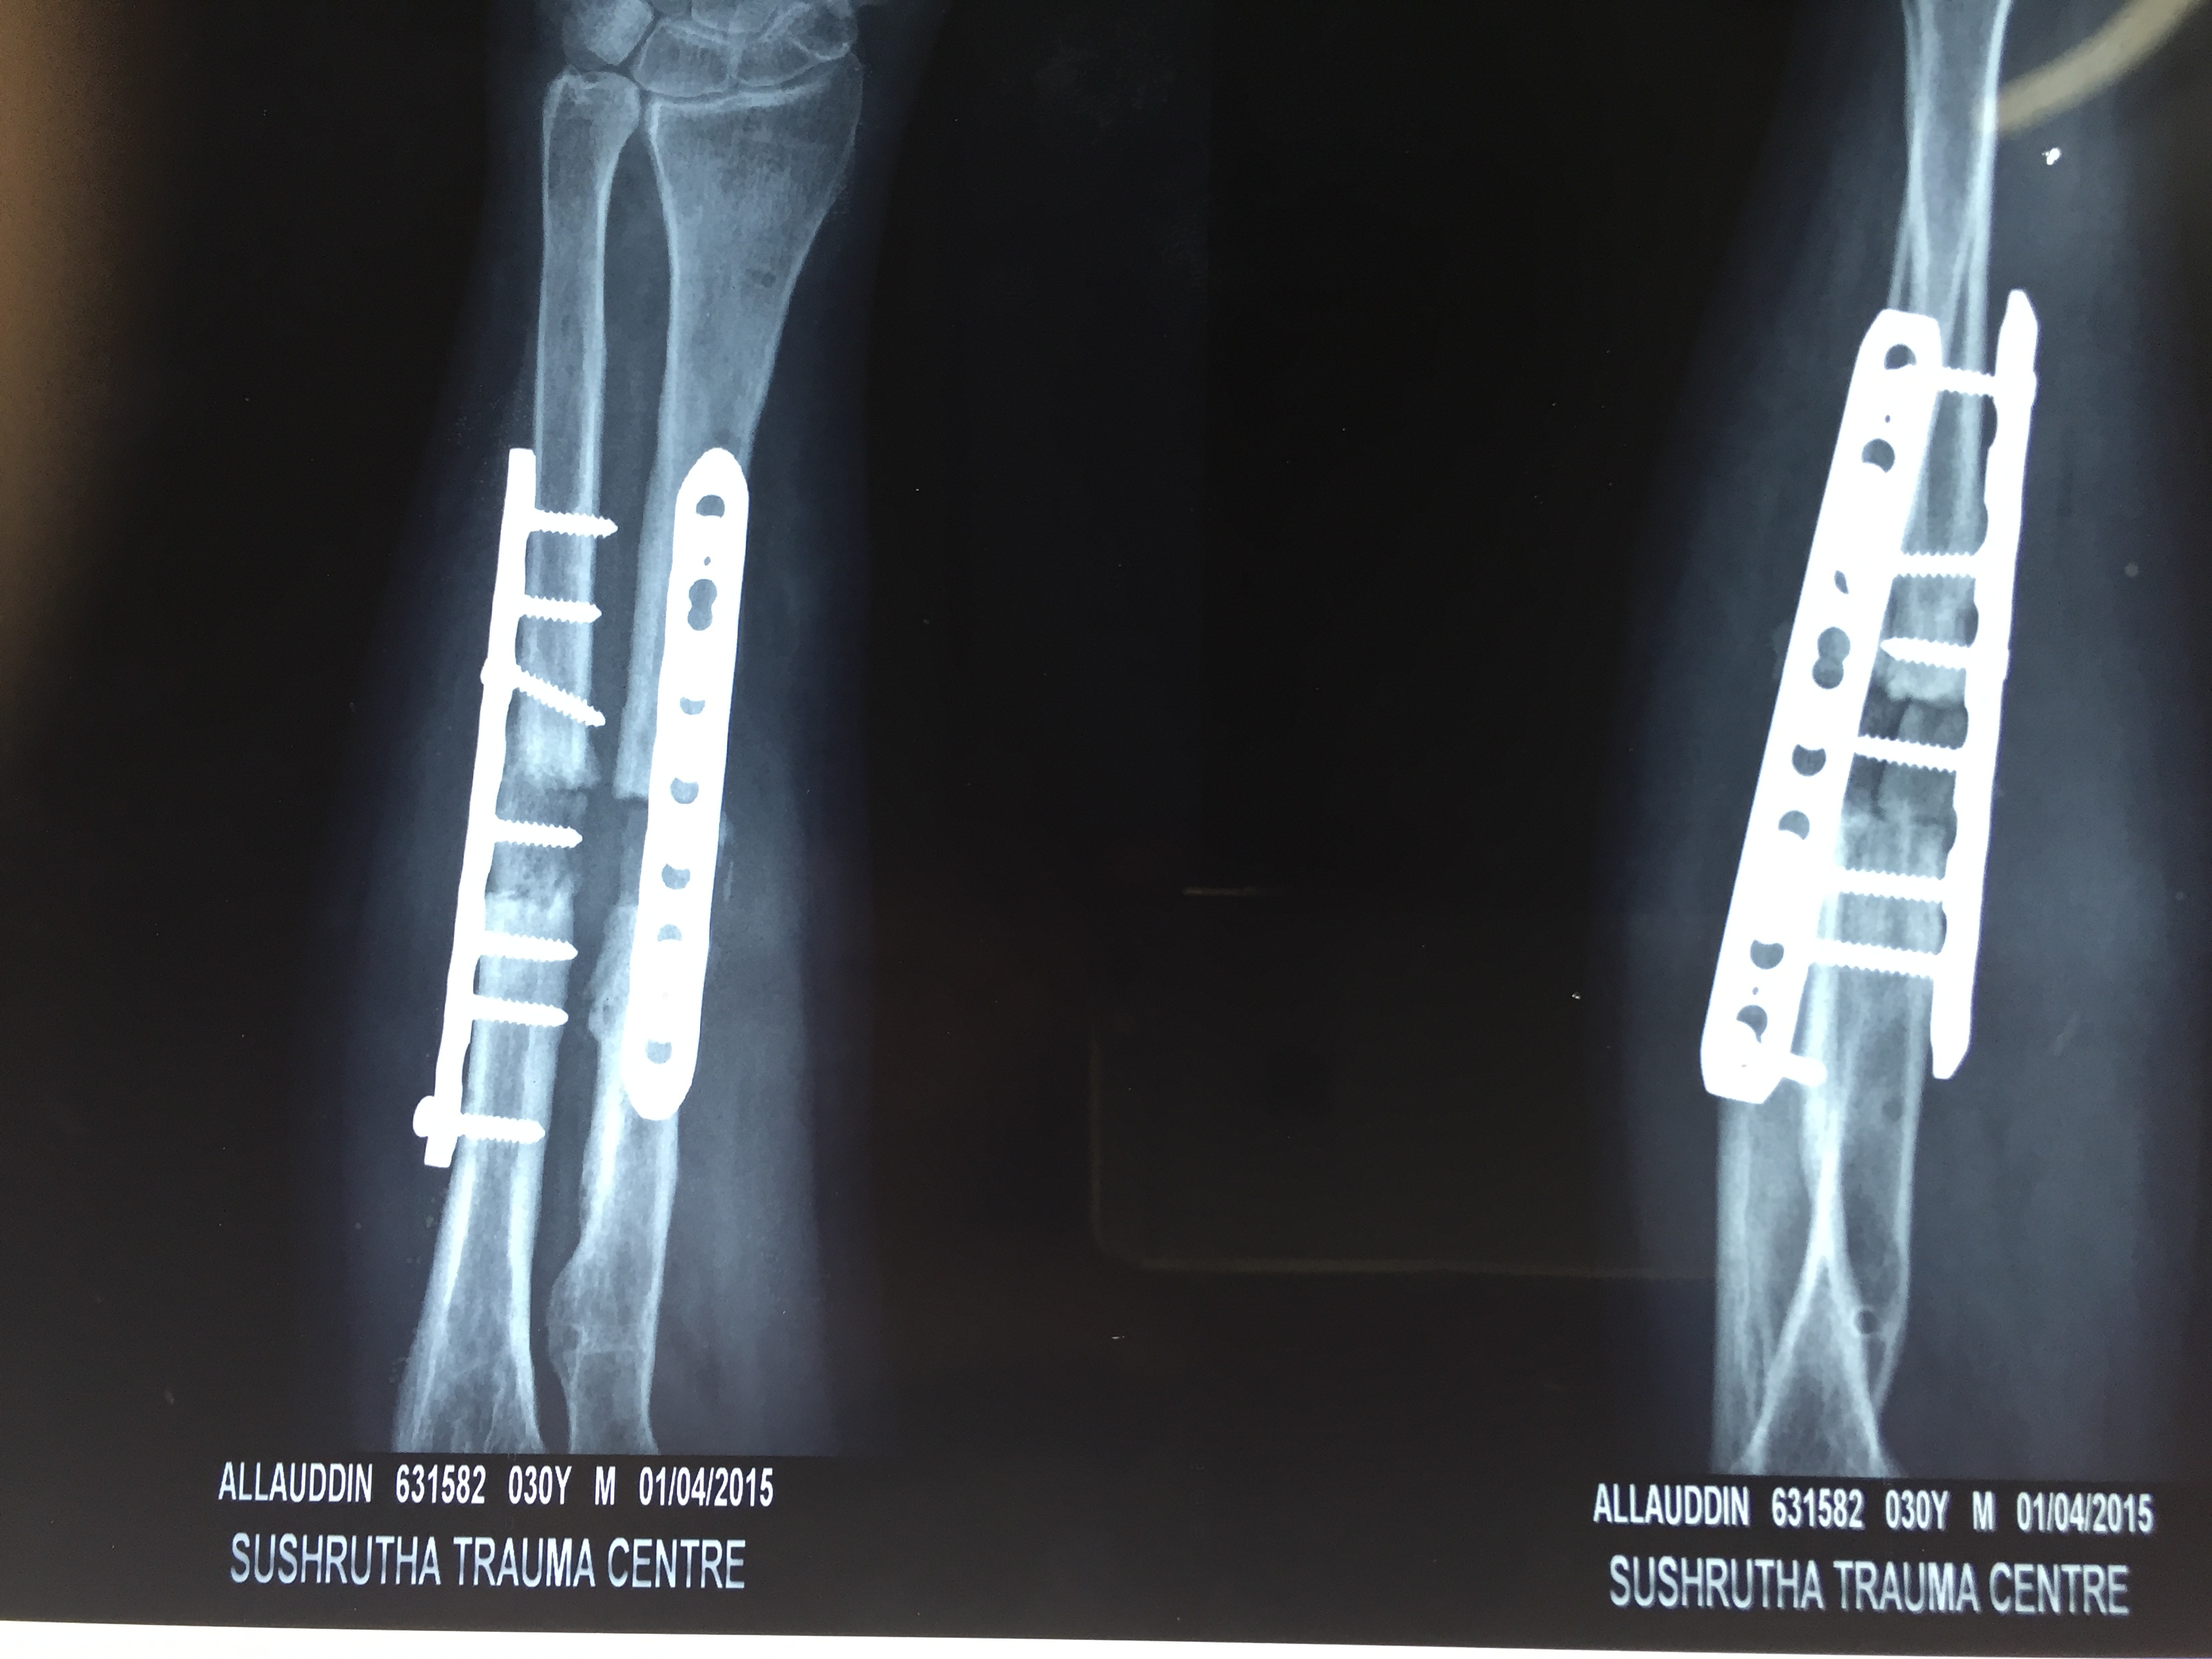

Once a medical professional has aligned the fracture, they will ensure it stays in place. Methods of doing so are –

- casts or braces

- metal plates and screws

- intramedullary nails, or rods, placed in bone cavities

- external fixings